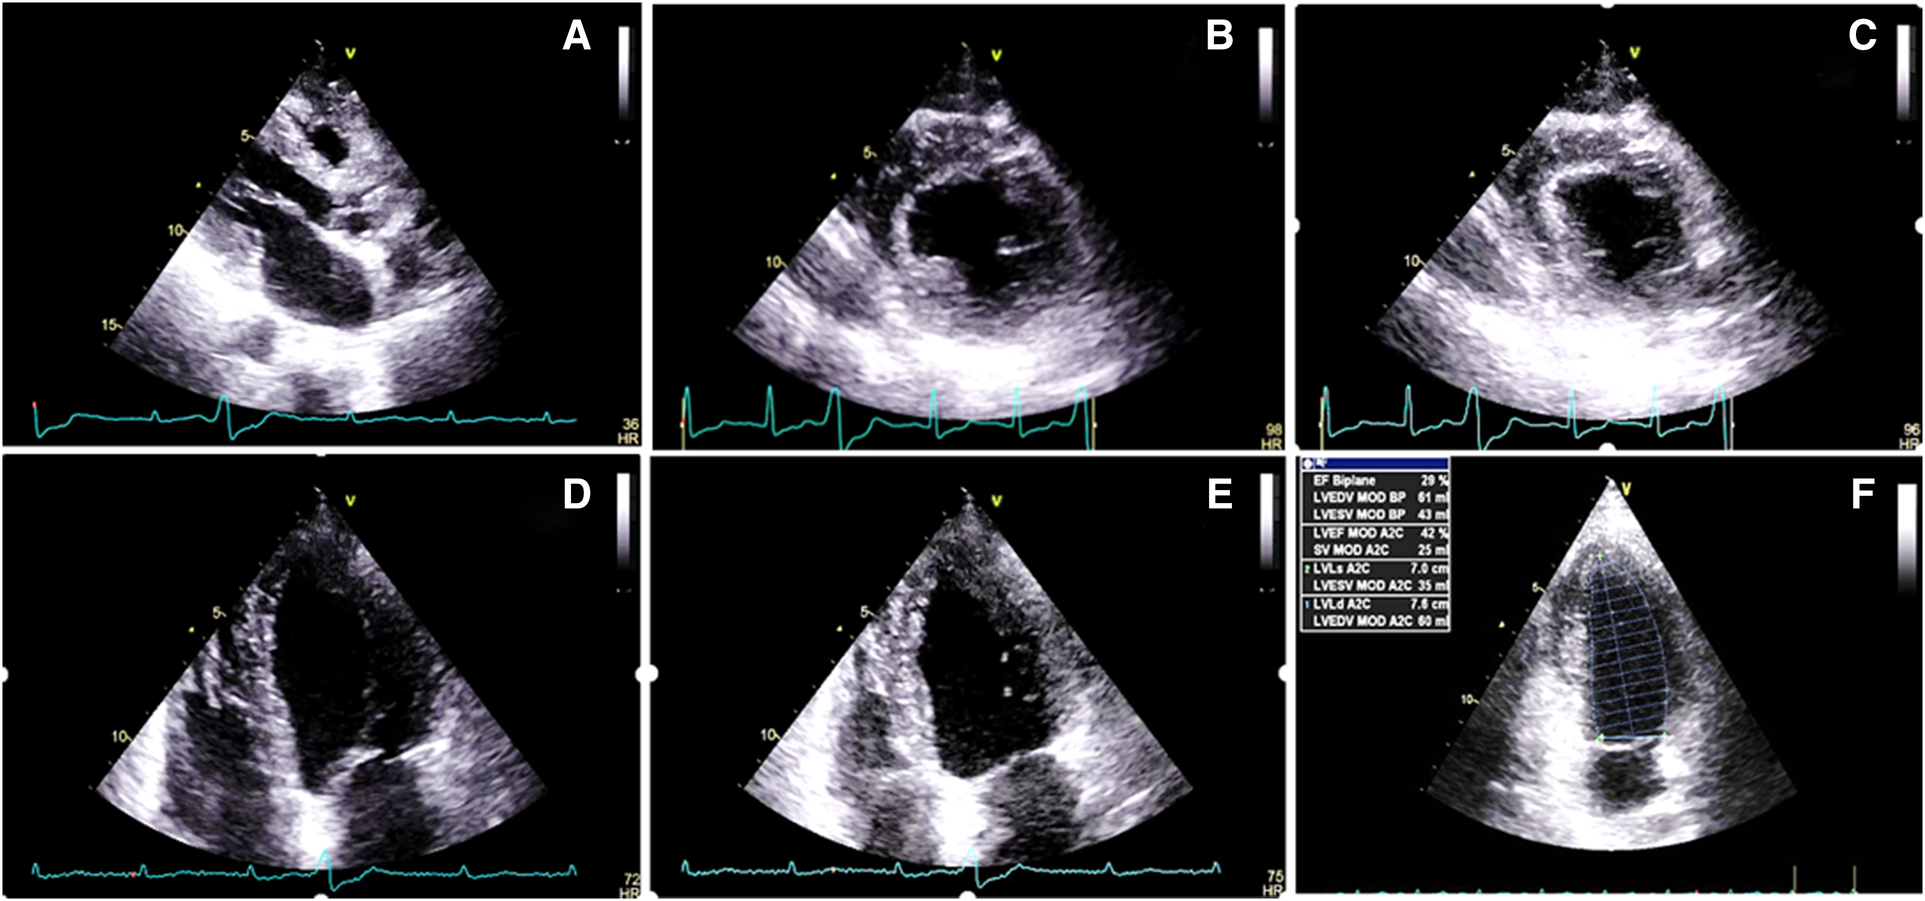

Figure 3

Two-dimensional transthoracic echocardiography 1 month after the radiotherapy course (A–F), illustrating a marked increase in the thickness of the left and right ventricular walls (15 and 7 mms, respectively), in addition to severe left ventricular systolic dysfunction. (A) PLAX view. (B) PSAX in the end-diastole. (C) PSAX in the end-systole. (D) A4C view in the end-diastole. (E) A4C view in the end-systole. (F) LV EF = 28% by Simpson's method. PLAX, parasternal long axis view; PSAX, parasternal short axis view; A4C, apical four chamber view.